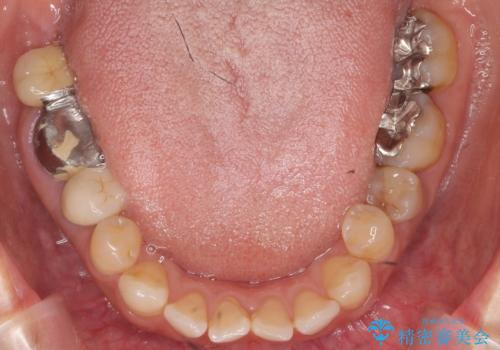

奥歯が割れている 抜歯してインプラントへ 40代女性

- 奥歯の痛みを主訴に来院された患者様です。

精査したところ、右下の奥歯(右下6)は割れており保存不可能な状態でした。

患者様のご希望により、右下大臼歯2本(右下76)のインプラント治療、右下小臼歯(右下5)の根管治療及び補綴治療を行いました。

インプラントの種類:ストローマン BLT

クラウンの種類:ベレッツァクラウン(右下76)、ジルコニアクラウン スタンダード(右下5)